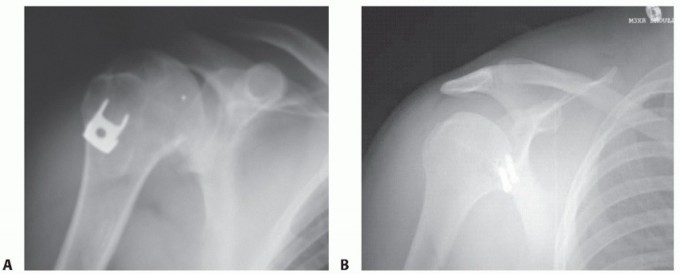

* FIG 3 • AP radiographs of the left shoulder showing a dislocated shoulder (A) and subsequent reduction

(B). There is a Hill-Sachs fracture of the posterolateral humeral head. C. Axial MRI scan in a patient with deficient glenoid labrum and subscapularis tendon tear.

Radiographs include anteroposterior (AP), lateral, and axillary views (FIG 3A,B). The axillary view is particularly important for assessing anterior glenoid rim defects.

The Hill-Sachs lesion of the posterosuperior humeral head is best seen on the AP internal rotation or Stryker notch views.

CT scan is not necessary in all cases but may be helpful in identifying patients with bony defects. Sagittal cuts and 3-D reconstructions are useful for quantifying the extent of glenoid bone loss (see FIG 2C,D).

Magnetic resonance imaging (MRI) scan is not necessary in all cases but can be useful in identifying labral lesions as well as concomitant rotator cuff tears (FIG 3C) or nondisplaced tuberosity fractures, which are more commonly seen in dislocations in patients older than 50 years of age.